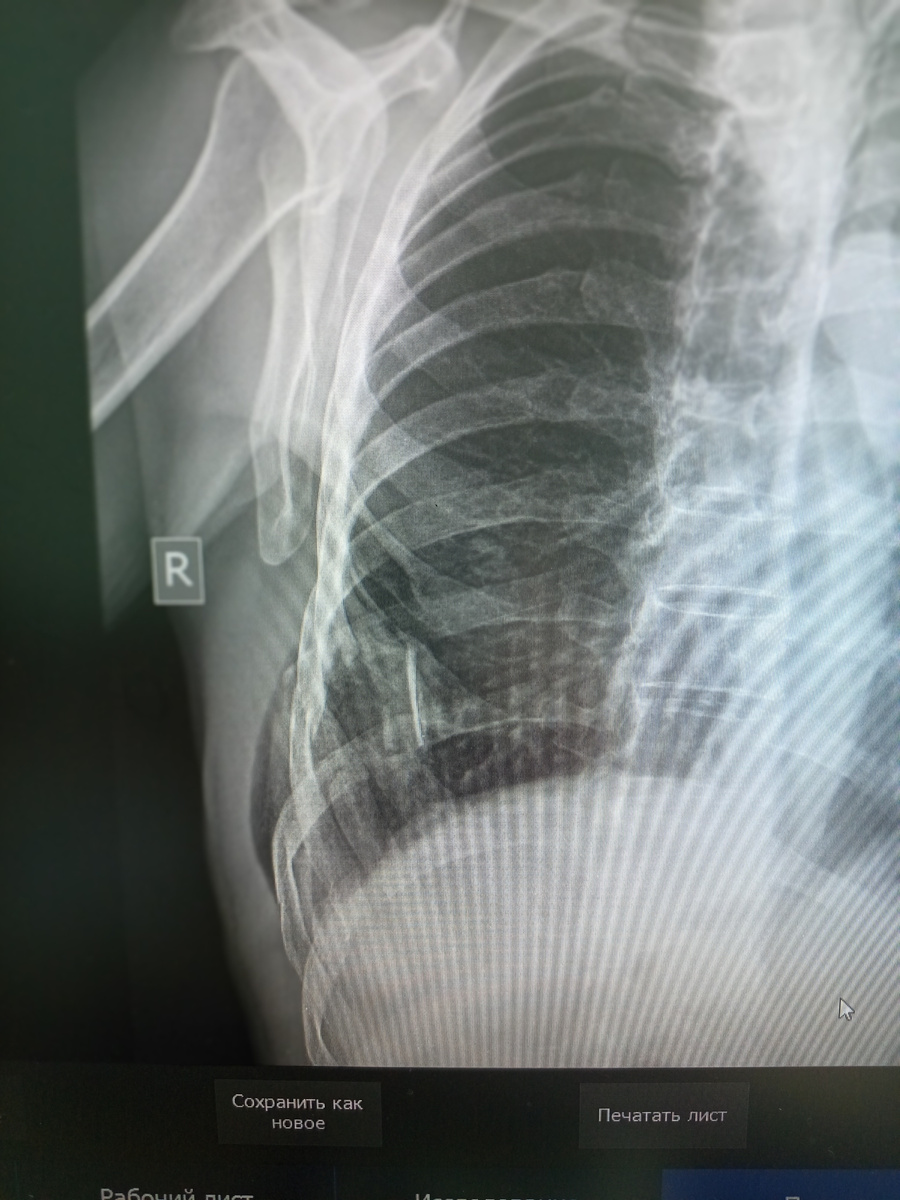

Пришел мужчина , 67 лет , на снимок сначала ребер , а потом и органов грудной клетки.

Явно у пациента негативный анамнез , упал где-то , на каких -то трубах , не помнит точно когда , но вот болит.

Видно , что есть переломы ребер, множественные.

А на снимке легких отчетливо видна подкожная эмфизема.